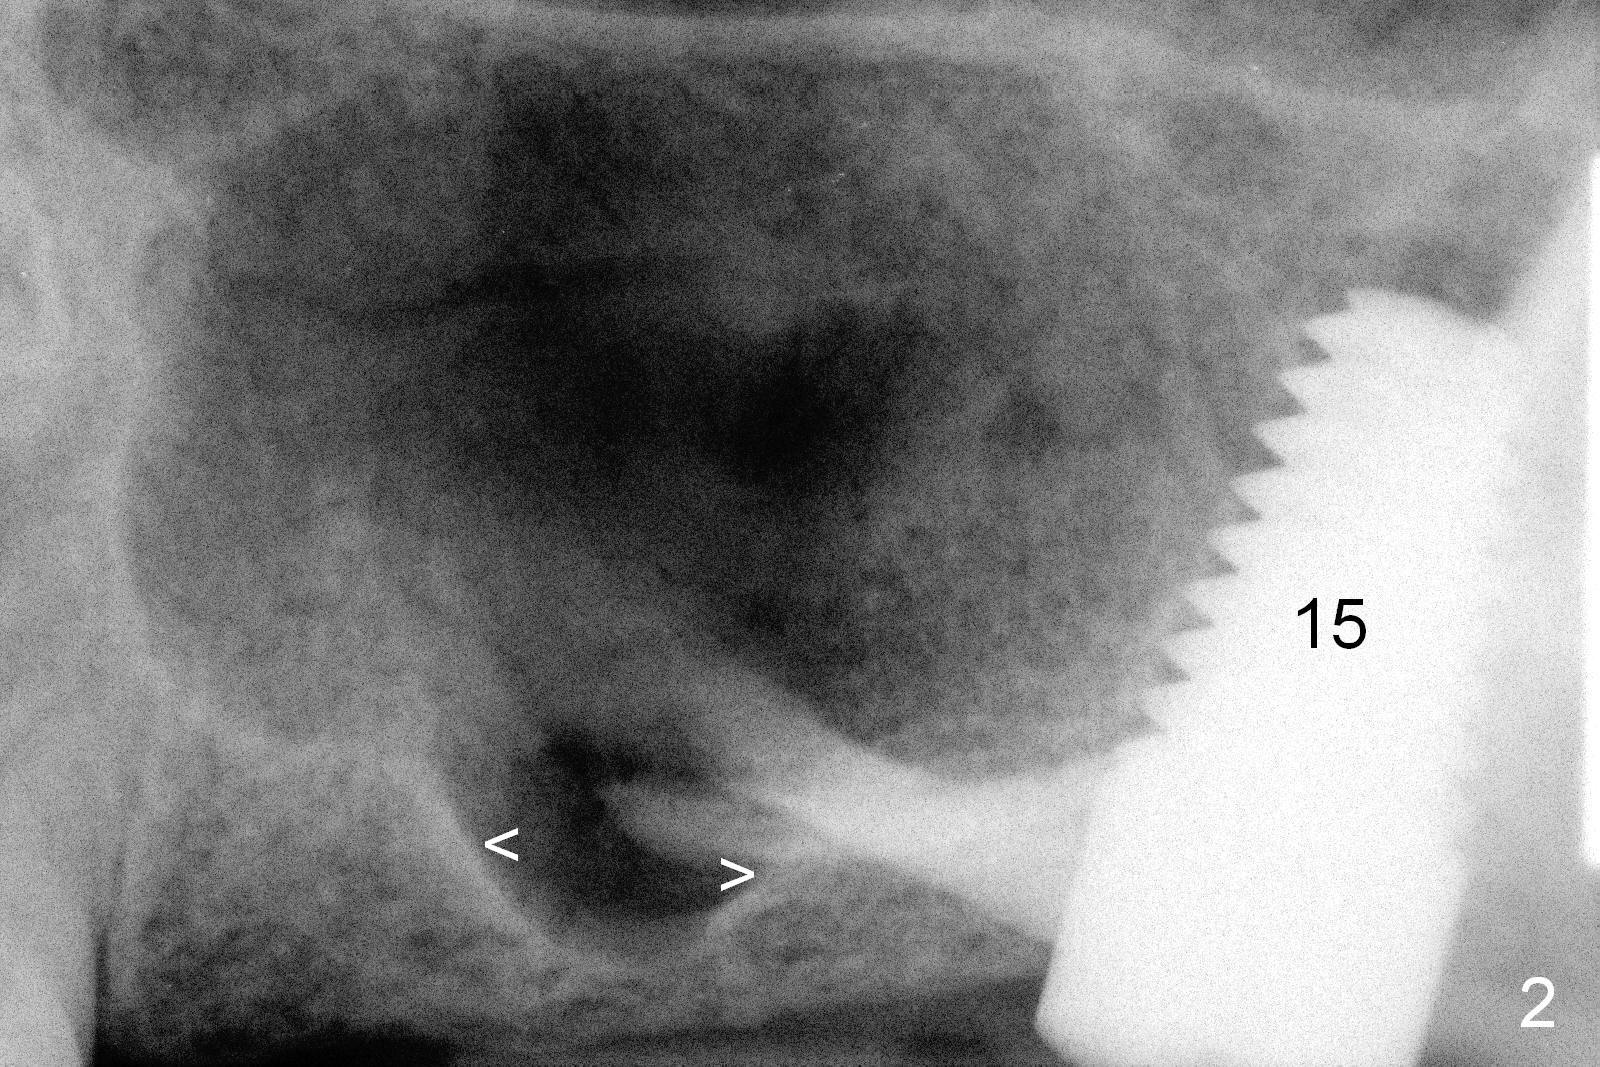

A man in his 70s had a partial denture in the upper left quadrant (Fig.1) prior to loss of #15, which was replaced by an implant (Fig.2). Lateral window sinus graft was tried without success in preparation for $14 implant placeement. Recently the partial was lost. Two missing teeth are going to be restored by implants with sinus lift in the crestal approach. Although the bone height is limited (2 mm), the implant at the site of #14 is able to obtain primary stability by engaging into the sides of the sinus floor (Fig.2 arrowheads).